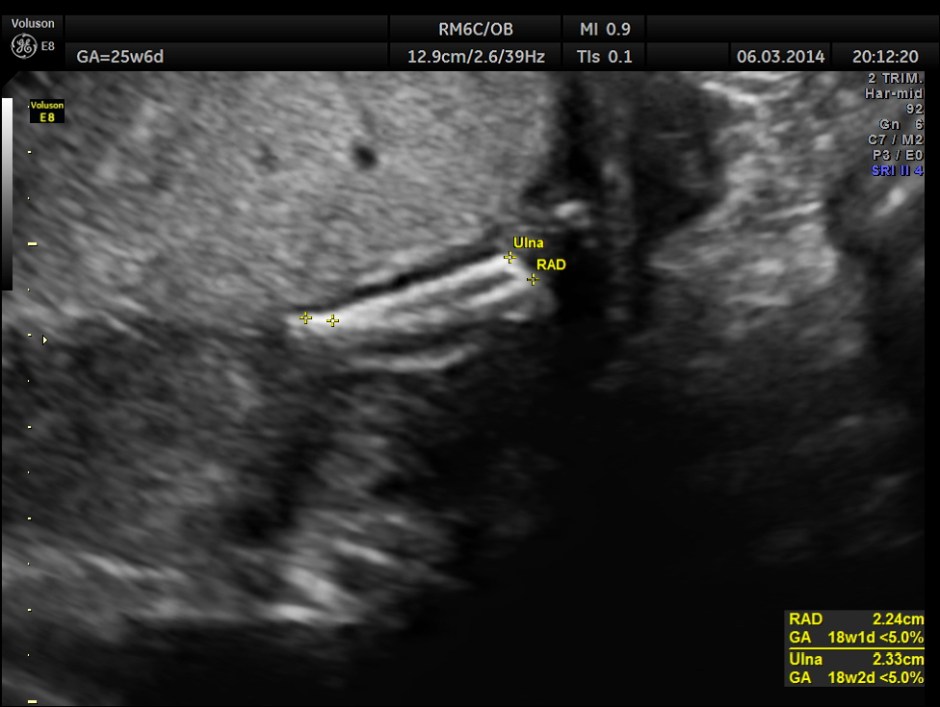

The GA was around 25 weeks , but the AUA was around 19 to 20 weeks. All parameters – BPD, HC, AC, FL are < 2.3 %tile and all other long bones are < 5.0 %tile.